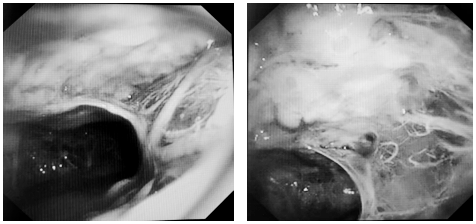

可视化清创:360°探查胸膜腔,精准清除脓苔及坏死组织。

靶向松解:活检钳、电刀分离致密粘连,恢复肺组织活动度。